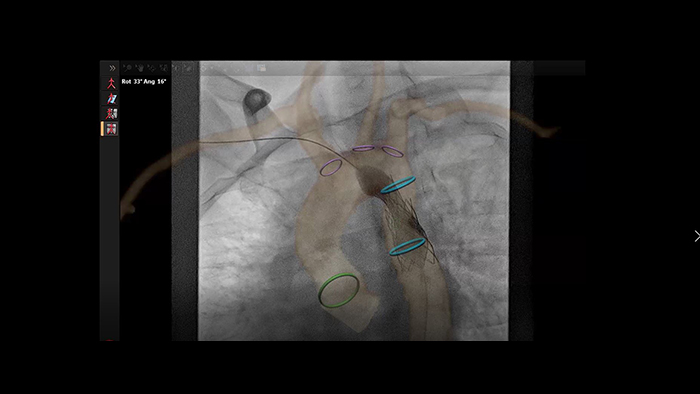

Aortic coarctation stenting guidance with VesselNavigator